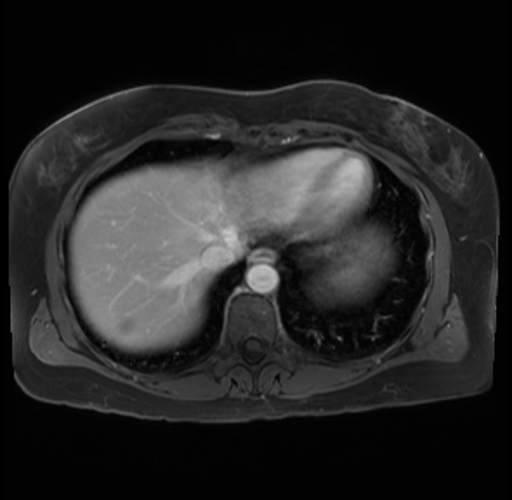

Imaging Analysis

Look through the patient's CT scan to identify any areas of concern for the necessary procedure.

Based on your CT findings, which issue(s) are present and would give reason for "planned slowing down moment(s)" in this case?